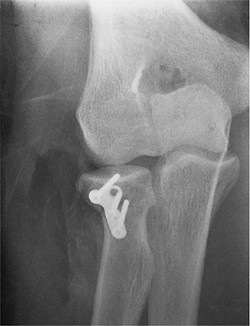

The technique described earlier was employed to insert a miniplate at

the margin of the radial head after the fracture was reduced (Fig. 5-17). At 1 year the fracture has healed (Fig. 5-18)

and the patient has a range of motion of 10 to 145 degrees, flexion of

70 degrees, and supination of 80 degrees. There is no pain.

![]() |

|

Figure 5-17. At reduction, the radial head was intact, and a miniplate was used employing the 1.0-AO cortical screws.

Figure 5-18.

One year after treatment the patient’s fracture has healed with minimal depression and the patient has a near-normal arc of motion. |